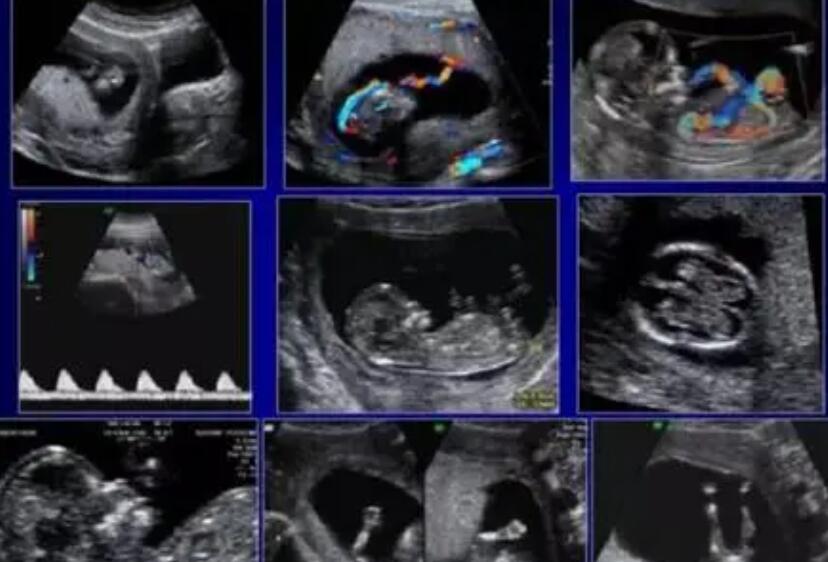

以后会做很多检查,nt检查是孕期常见的检查方法。很多孕妇特别好奇怀孕后怀的是男的还是女的。可以在他们想第一时间知道后,为他们准备衣服和用品。我们来看看nt。NT考试能分男女吗?T检验会在孕11-14周之间进行,因为11周之前的检验不明显,胎儿还太小。14周后胎儿皮下积液会被淋巴吸收,无法做出正确的检查数据。所以孕妇需要在这个周期内做nt检查。因为nt检查时不需要抽血,所以孕妇不用空腹。Nt检查要提前11周,以免排队,检查最佳时间已过。

一般来说,NT检查值暗示着胎儿的性别是孕妈妈根据自己的经验总结出来的。毕竟生男生女的概率是50/50,不管怎么猜,总有50/50的几率是对的,所以这些说法一直流传下来。Nt报道没有看出是男生还是女生的招数,不采取这种网上传播的方法。nt报告中显示的婴儿图像只是截取了一个模糊的图例,没有办法看清生殖器官。nt报告中没有男女婴儿的区别,也不能作为判断出生的是男是女的标准。即使通过超声波观察胎儿的外生殖器,也无法准确判断,因为胎儿的外生殖器在孕12周时还没有发育成熟,所以很难区分性别,猜测也很难知道结果。

nt检查主要是检查胎儿颈部透明带的厚度。如果能尽早判断是否有染色体疾病,就不能检查出男女。性别是通过腹部b超检查的,国家有规定不能鉴定胎儿性别。无论是男宝还是女宝,在受精怀孕的那一刻就已经形成了。其实只要胎儿发育好,各项指标都正常,男孩女孩都一样。以上就是关于已生女孩的nt值是多少?男孩女孩nt值有什么区别?的全部内容。如果还有疑惑的话欢迎咨询592宝宝网试管资讯分享平台的专业生殖顾问。祝您好孕~